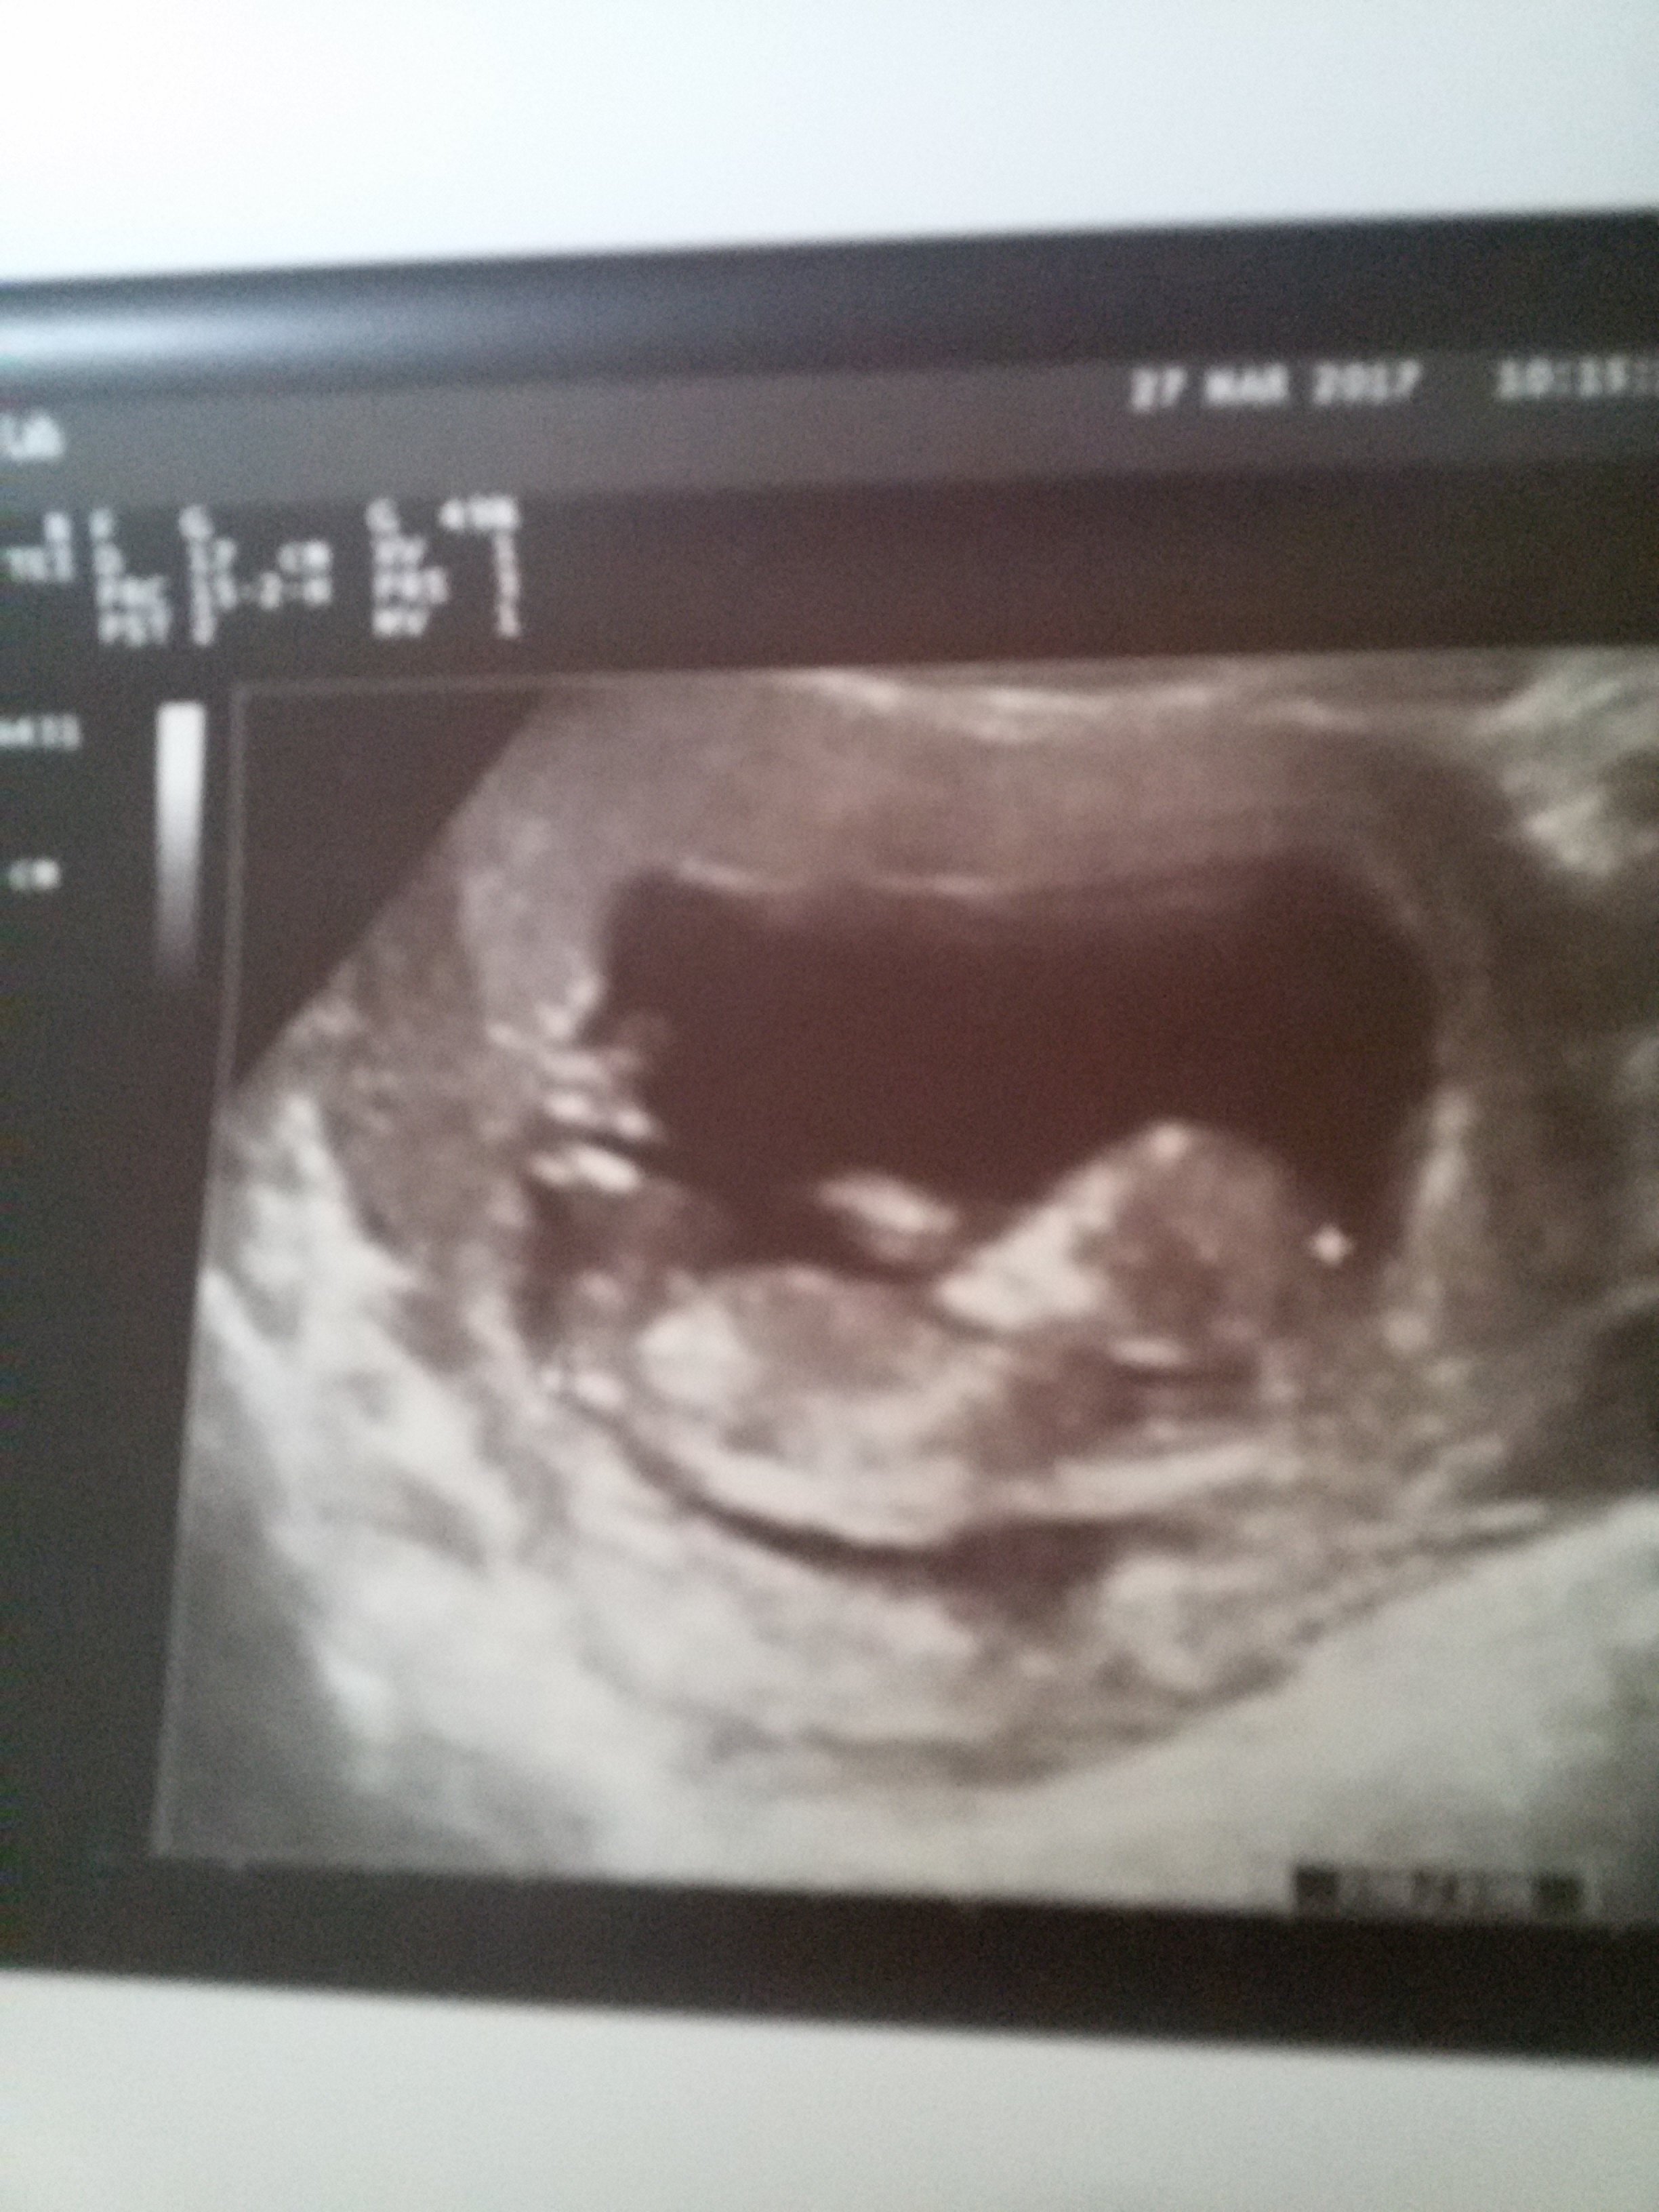

Dziewczyny, czy wy macie takie uplawy coś w stylu takiego gluta? Nie wiem czy się martwić, byłam w piątek na wizycie i zapomniałam o tym powiedzieć co prawda jeśli chodzi o dziecko to na usg wszystko było dobrze.